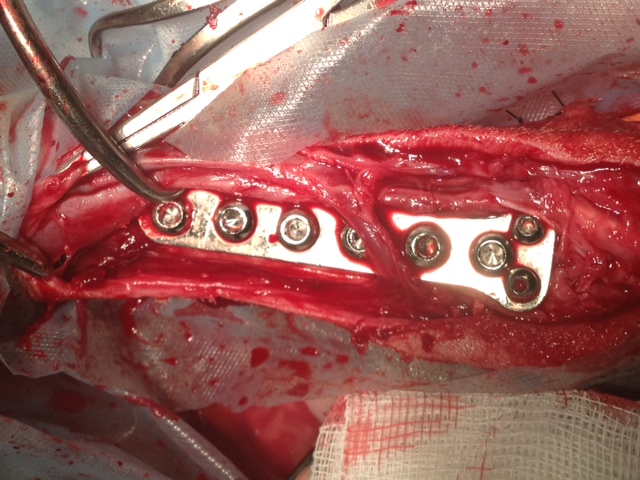

Heute hatte Felipa ihren ersten OP-Termin.

Wir waren alle sehr aufgeregt. Und selbst der erfahrene Arzt meinte, es sei eine ungewöhnliche Aktion, denn normalerweise weist nur ein Pfötchen so starke Anomalien auf. Er hatte es noch nicht, dass beide operiert werden müssen.

Felipa war relativ unbeeindruckt von der ganzen Geschichte und tanzte schon kurz nach dem Eingriff wieder auf dem Tisch herum.